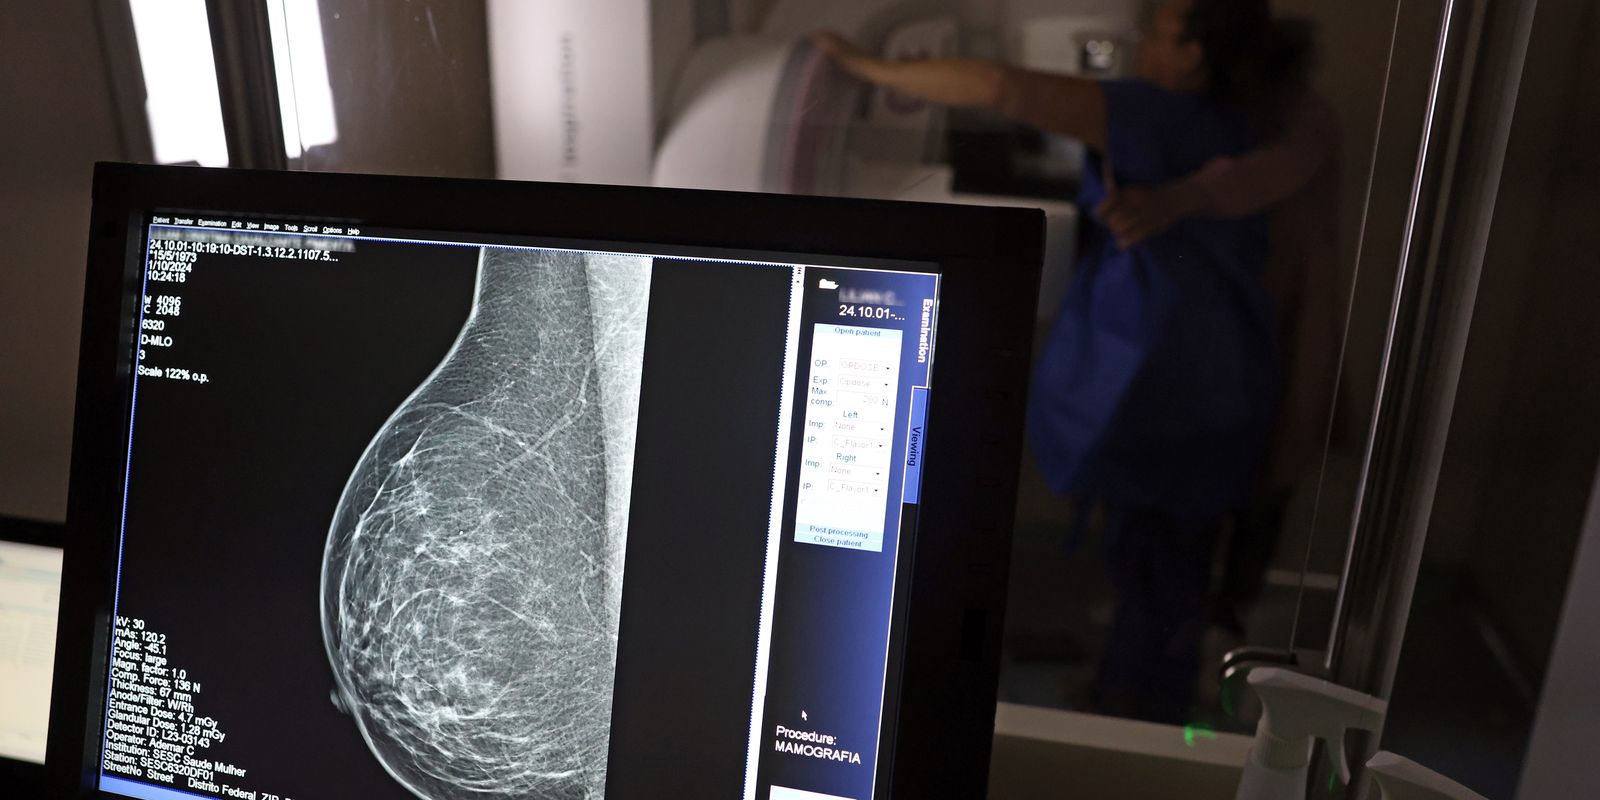

No mês de conscientização sobre o câncer de mama, um relatório destaca a importância de acesso igualitário ao rastreamento e tratamento da doença. Segundo o Atlas da Radiologia no Brasil, do Colégio Brasileiro de Radiologia e Diagnóstico por Imagem (CBR), o acesso aos mamógrafos ainda é um desafio.

O país tem 6.826 equipamentos registrados, sendo 96% em funcionamento. Metade deles está disponível no Sistema Único de Saúde (SUS), responsável por atender 75% da população. Isso equivale a 2,13 mamógrafos por 100 mil habitantes dependentes do SUS.

Na saúde suplementar, que cobre 25% da população, o cenário é mais favorável: 6,54 aparelhos por 100 mil beneficiárias, quase o triplo da rede pública. O Acre exemplifica essa disparidade — são 35,38 mamógrafos por 100 mil habitantes na rede privada, contra 0,84 no SUS.

Há disparidades regionais. Roraima tem a menor proporção (1,53 por 100 mil), seguida do Ceará (2,23) e Pará (2,25). A Paraíba lidera o ranking (4,32), à frente do Distrito Federal (4,26) e do Rio de Janeiro (3,93).

O Brasil tem uma cobertura muito baixa de mamografias: 24%. O ideal recomendado pela Organização Mundial da Saúde é de 70%. Mesmo em lugares como o estado de São Paulo, que tem a maior concentração de mamógrafos do país, a taxa gira em torno de 26%.

Em setembro, o Ministério da Saúde ampliou as diretrizes de rastreamento, recomendando que mulheres entre 40 e 49 anos realizem mamografias, mesmo sem sintomas. De acordo com o Instituto Nacional do Câncer (Imca), mais de 73 mil mulheres recebem o diagnóstico de câncer de mama anualmente no Brasil.

“O que é efetivo na redução da mortalidade é você descobrir o tumor antes de ter sintoma clínico. Quanto menor o tumor, melhor para a gente descobrir o tratamento e maior a chance de cura. E a gente só consegue fazer isso com exames de imagem”, diz Ivie.

Ela explica que no caso de diagnóstico de um câncer de mama com menos de 1 cm, a chance de cura é de 95% em cinco anos, independentemente se ele é do tipo mais agressivo. “E esses tumores só vão ser detectados na mamografia. Essas pessoas que têm que ir fazer mamografia são mulheres saudáveis. Não são mulheres doentes”, acrescenta.